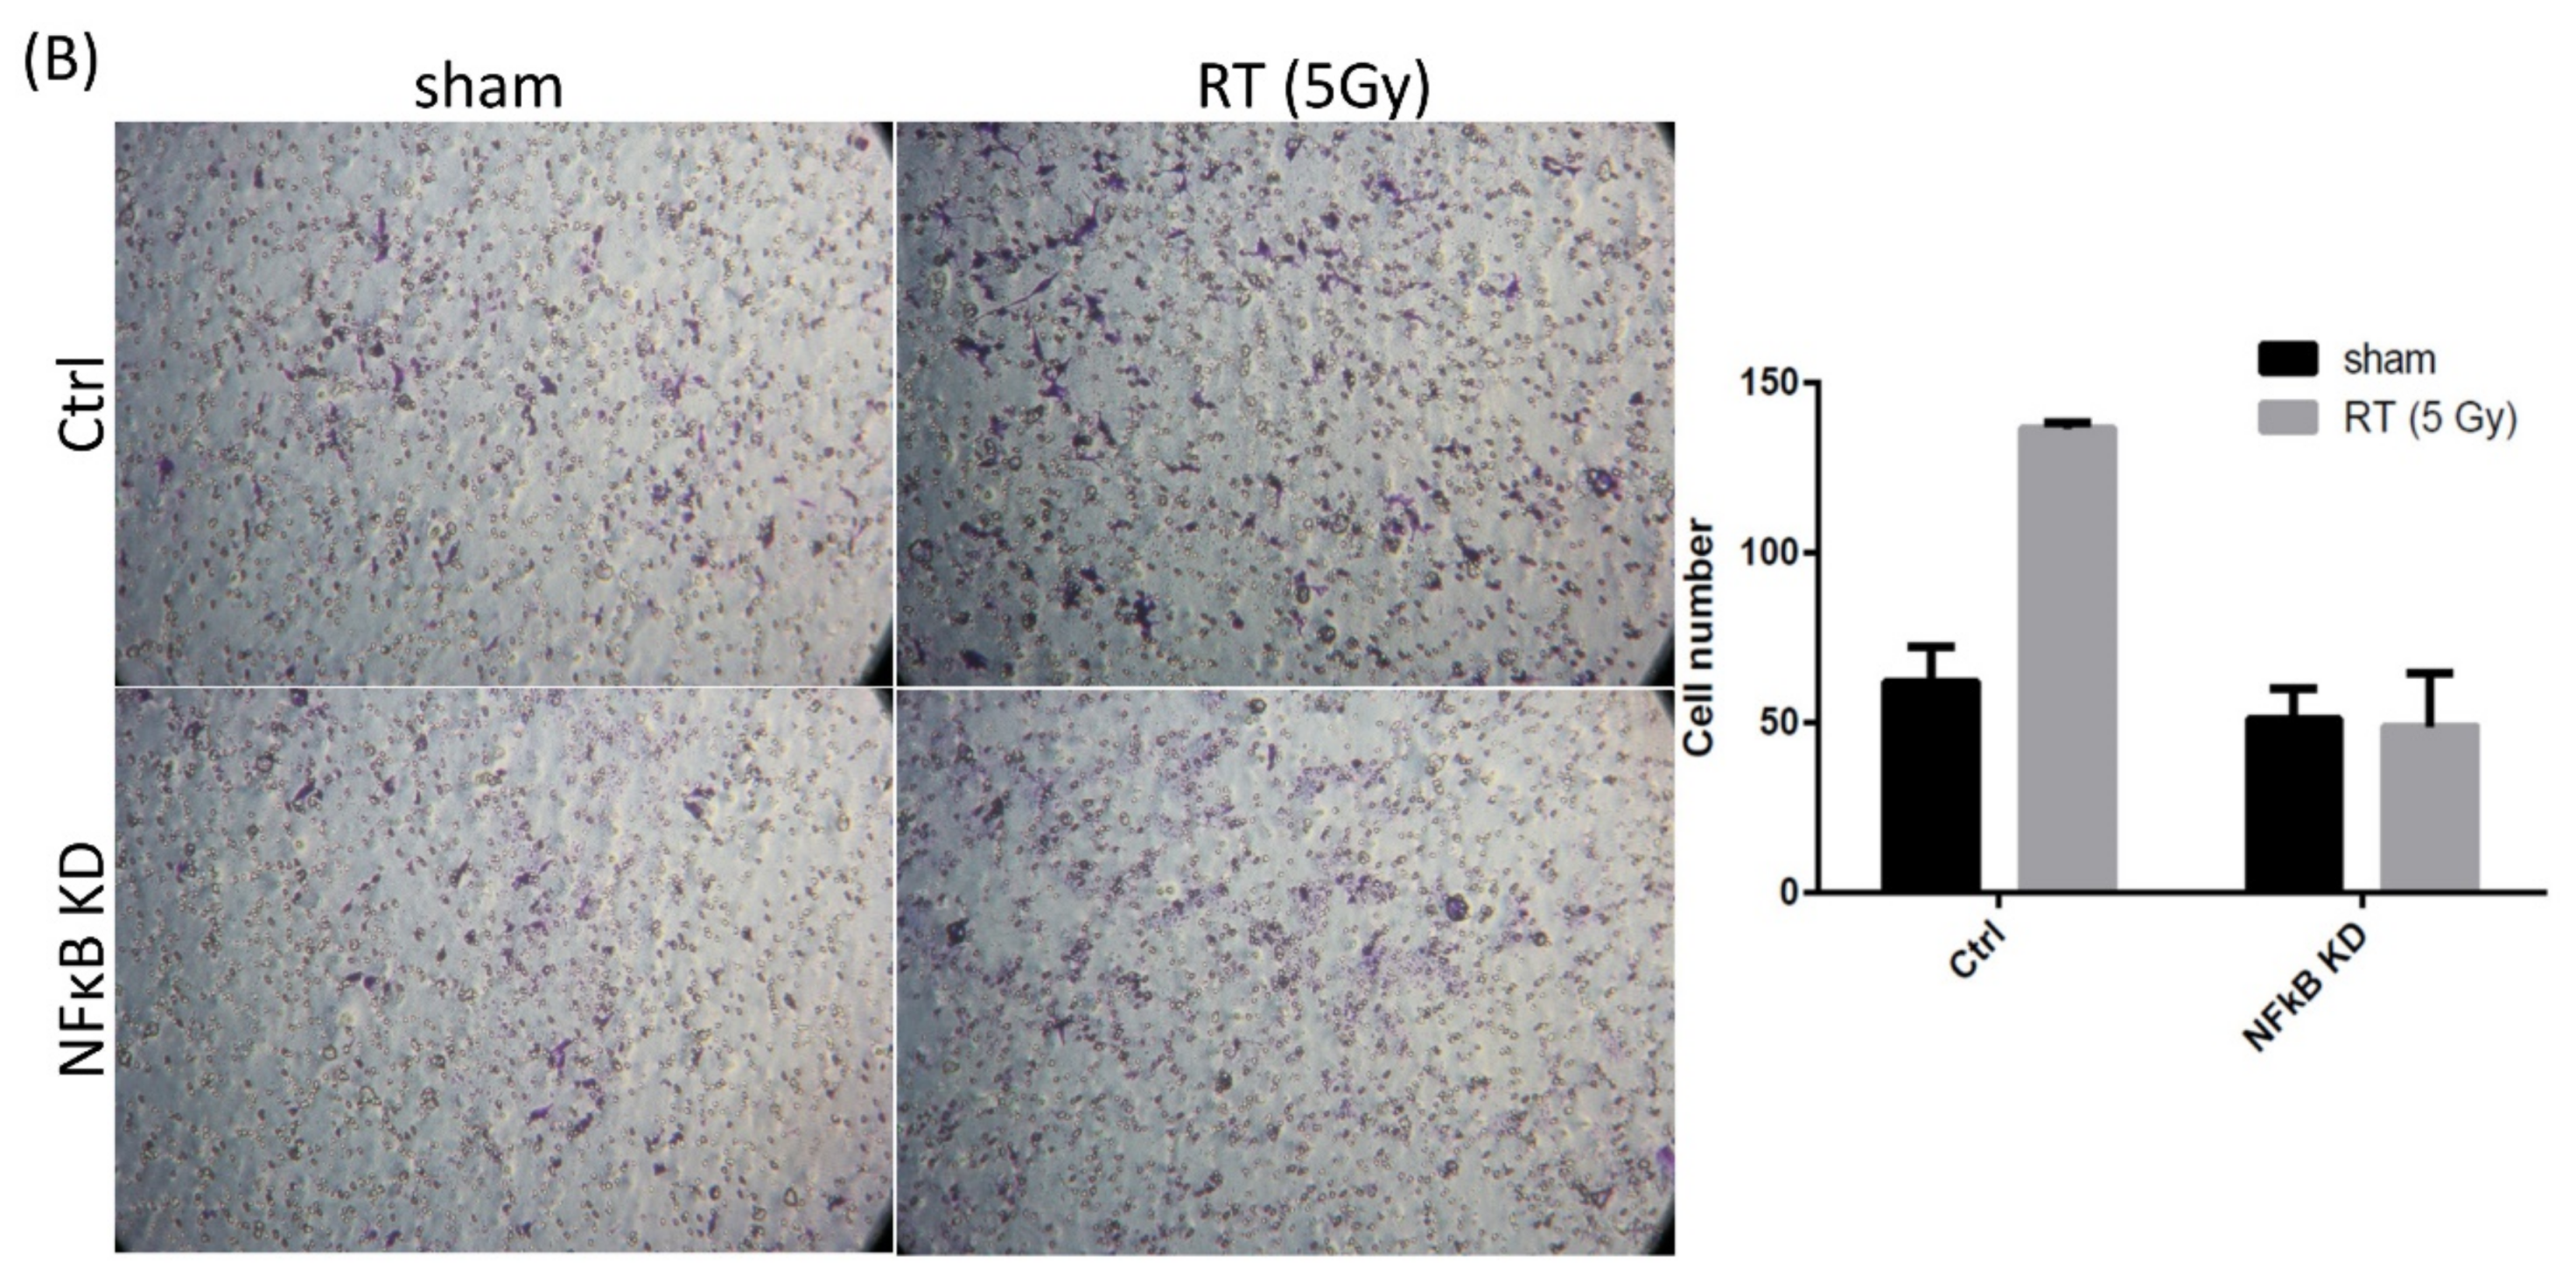

3.4. In Vitro Investigation of NFκB Expression of Irradiated Bladder Cancer Cells